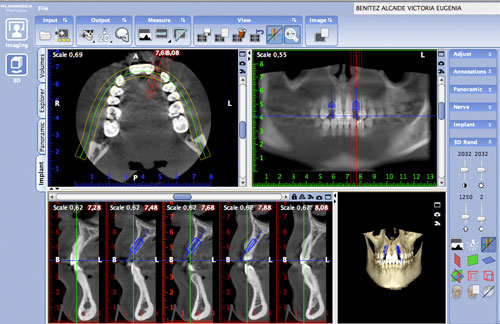

En la panorámica se observa la presencia de ambos 3º molares superiores y la agenesia de los inferiores así como de los laterales motivo de la consulta , y en la rx simple en proyección dorso palmar de su mano, observamos el cierre de todas las fisis o cartílagos de crecimiento, lo que indica una maduración esquelética completa.

Decidimos entonces tomar una nueva panorámica y realizar un Índice de Scarpa para corroborar su edad ósea.

Ante el estudio de scanner de haz de cono, la situación ósea es normal, de un hueso densidad tipo 4 (entre 155 y 237 UH a distintos niveles del hueso remanente) de un ancho vestíbulo palatino e inciso apical adecuado, pero inter dentario escaso.

Esto nos obliga a utilizar implantes extremadamente delgados de 2,8 mm por 12mm de la marca BREDENT.